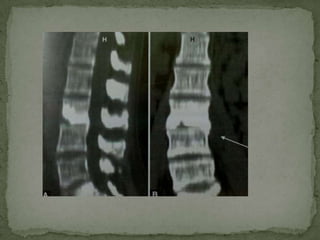

 MRI Scores over CT in-

 Detection of early disease (marrow edema)

 Skip lesions more easily and more often detected.

Incidence of multilevel noncontiguous vertebral

tuberculosis is generally reported to be between 1.1 and 16

%